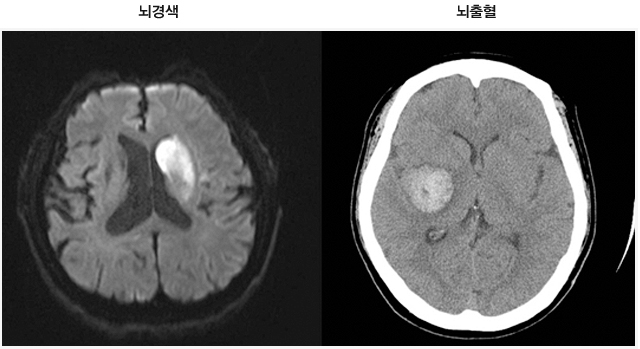

뇌혈관이 막히거나 터지는 질환을 부르는게 뇌졸중이고 그 중 뇌혈관이 막히는게 뇌경색 그리고 뇌혈관이 터지는 것을 뇌출혈이라고 합니다. 뇌졸중은 영구적인 손상이 많다고 하며 증상에 따라 전신이나 육체 일부 기능이 마비되는 등의 극심한 후유증이 남는 무서운 질병입니다 오늘은 뇌경색 초기증상에 대하여 알려드리도록 하겠습니다.

허혈성 뇌졸중은 발생 기전에 따라 대혈관 질환에 의한 뇌경색, 심인성 뇌경색 또는 심인성 뇌경색, 소혈관 질환 또는 틈새 뇌경색, 기타 드문 이유가 되는 것에 의한 뇌경색으로 나누어져요. 에피소드는 일정 기간 동안 증상이 완전히 가라앉는 경우입니다.

허혈성 뇌졸중의 대표적인 이유가 되는 것은 고혈압, 당뇨병, 고지혈증 등으로 인해서 뇌에 혈액을 전달하는 혈관에 동맥경화(동맥경화)가 발생하여 뇌로 가는 혈류를 차단하는 것입니다.